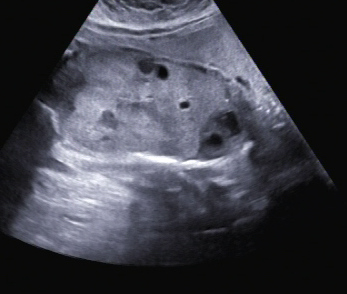

Ein zunächst durchgeführtes CTG war unauffällig. Im Rahmen der sonografischen Untersuchung zeigte sich der Fötus soweit beurteilbar zeitgerecht entwickelt. Dennoch konnte ein Anhydramnion festgestellt werden(Abb. 1, 2), weshalb auch kein fetales Gesicht darstellbar war (Abb. 3).

Im Abdomen war die Blase nicht gefüllt darstellbar (Abb. 4).